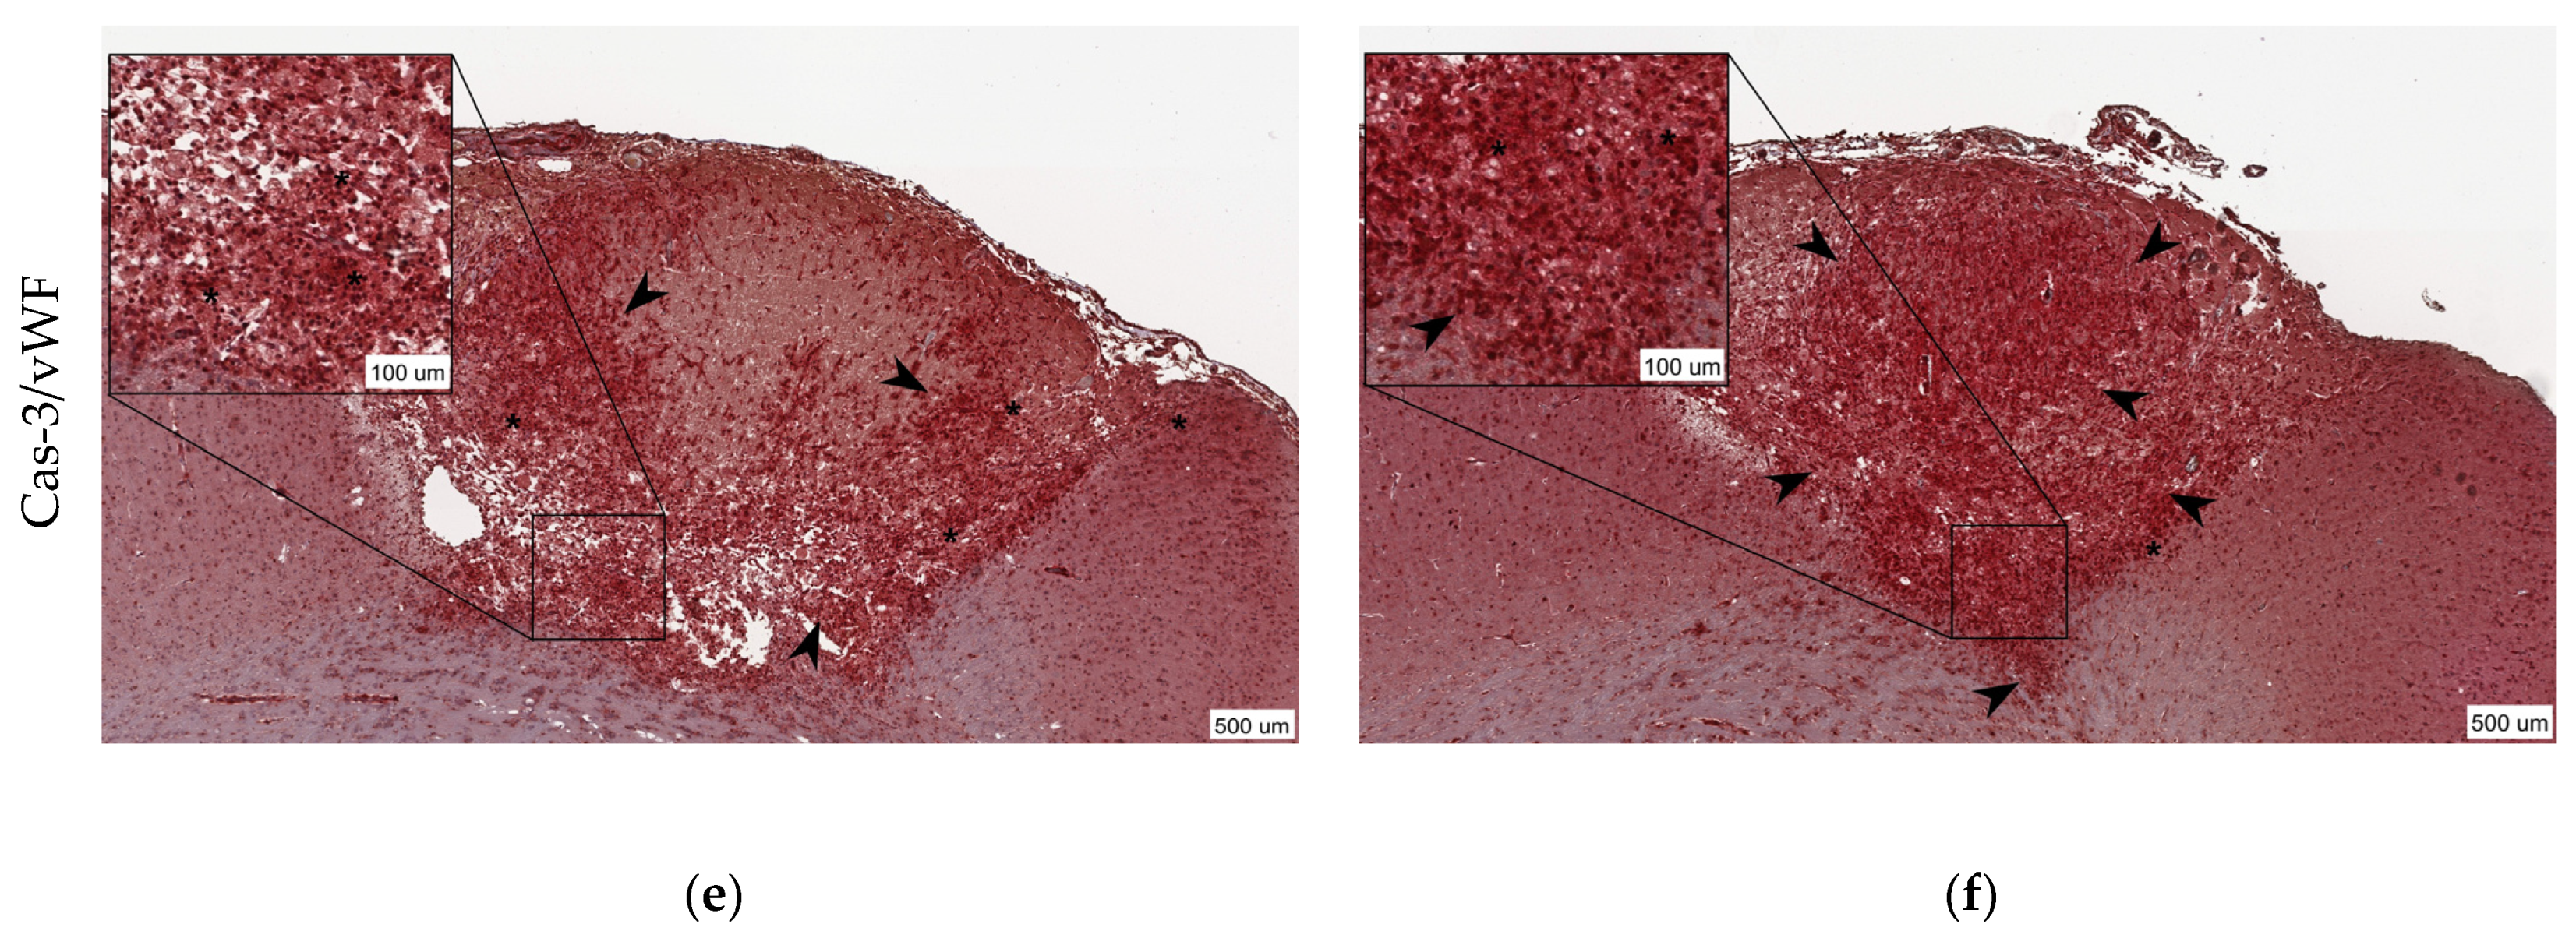

3.2. Krypton Inhibits Neuroinflammation and Cell Death after Ischemic Stroke